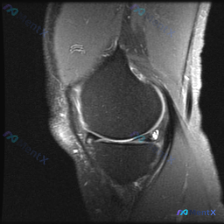

今天遇到一个挺有代表性的病例,主诉提示膝关节半月板异常,只提供了单张膝盖MRI冠状位T1加权像,整理一下分析思路跟大家分享。 一、病例核心信息 核心问题:患者主诉提示半月板异常,仅提供单一层面冠状位T1加权MRI读片 影像观察结果: 1. 骨骼:股骨远端、胫骨近端骨皮质完整连续,骨髓腔T1信号为均匀...